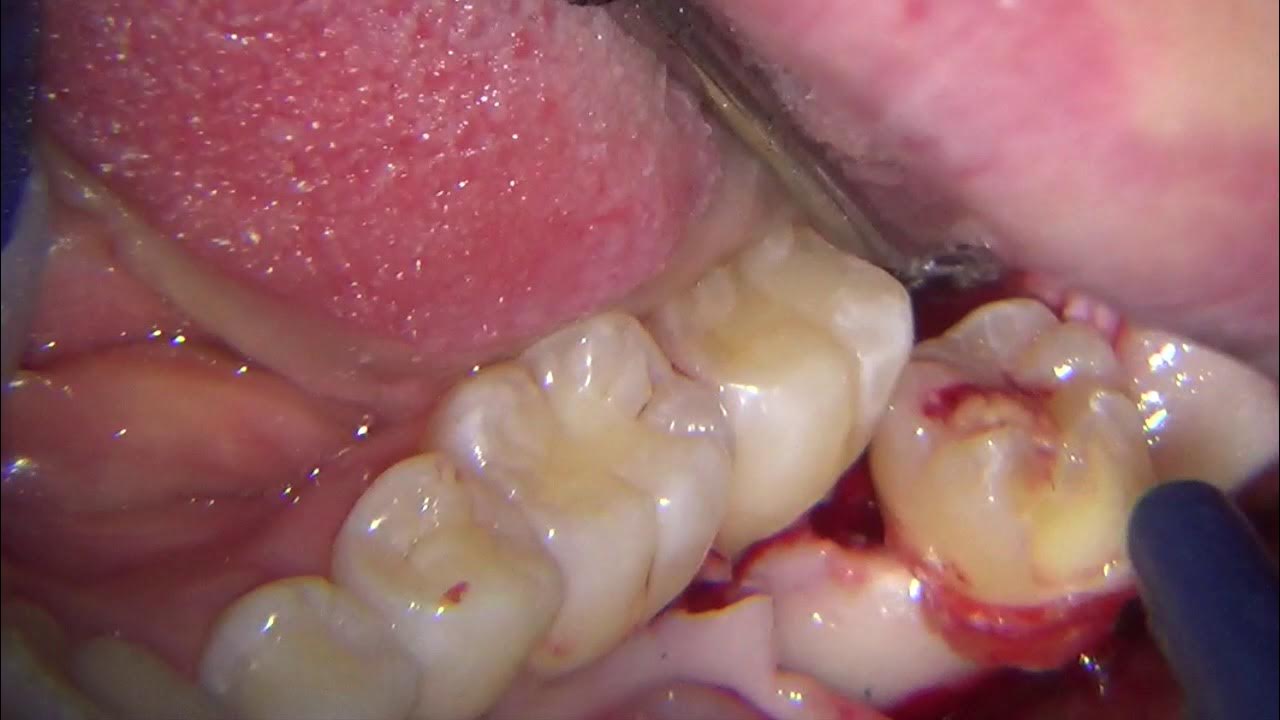

Mesioangular impacted wisdom tooth removal Third molar extraction Third Molar Extraction Ce Courses The ultimate third molar extraction course. Master the techniques for safe and effective. He is internationally known and. We replace your fear and frustration with knowledge and confidence to safely and. Understand the anatomical considerations and potential complications of third molar surgery. Become faster, more efficient and proficient with impacted third molar extractions. Recognize and understand radiographic imaging modalities to. Third Molar Extraction Ce Courses.

Unedited surgical extraction of partially erupted upper third molar Third Molar Extraction Ce Courses Recognize and understand radiographic imaging modalities to assess possible risks involved in third molars or complicated extractions. He is internationally known and. Become faster, more efficient and proficient with impacted third molar extractions. Master the techniques for safe and effective. Understand the anatomical considerations and potential complications of third molar surgery. The ultimate third molar extraction course. We replace your. Third Molar Extraction Ce Courses.